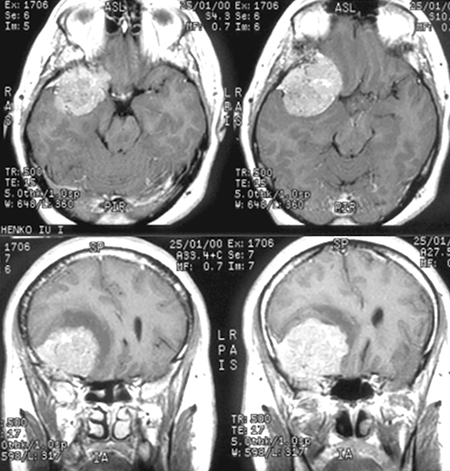

Парасагиттальные менингиомы (ПСМ)

К парасагиттальным относятся менингиомы, связанные с верхним сагиттальным синусом (ВСС) и большим серповидным отростком (БСО) (рис. 2). Менингиомы ВСС встречаются чаще и составляют около 75% ПСМ. В западной литературе менингиомы БСО традиционно выделяются в отдельную группу.

Рисунок 2. Парасагиттальная менингиома средней трети верхнего сагиттального синуса, с большим гиперостозом и интракраниальным узлом (МРТ, Т1-взвешенные изображения, с контрастным усилением). Синус полностью проращен опухолью